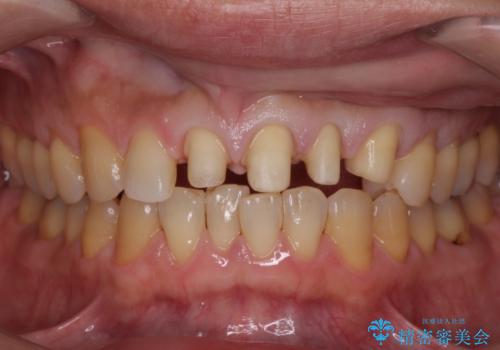

転んで前歯が欠けてぐらぐらに 歯の神経も死んでしまった

- 転倒して前歯を強打してかけてしまった、ぐらつくとのことで来院。

応急でみてもらった歯科医院で隣の歯と接着剤で留めてもらったとのこと。

歯の神経の状態を見たところ、前歯3本とも神経が死んでしまっていました。

また、左上犬歯の詰め物は途中で脱離し、セラミックでの修復をご希望されたため、一緒に治療しました。

根の治療を行い、ぐらつきに関しては様子を見て連結をするとのお話をさせていただきました。

結果ナイトガードの使用によりぐらつきはだいぶ回復してきたため連結はしていません。